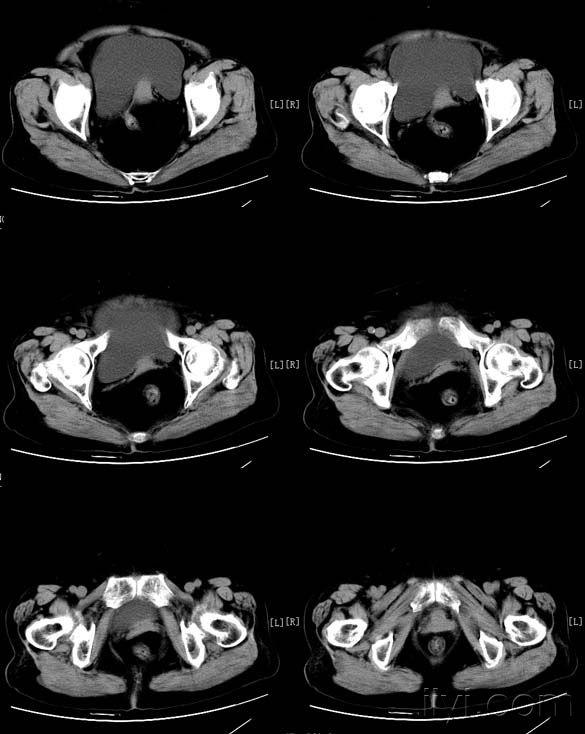

盆腔病变(卵巢乳头状浆液性囊腺瘤 )

诊间日记:双侧卵巢浆液性囊腺癌

图片尺寸828x620